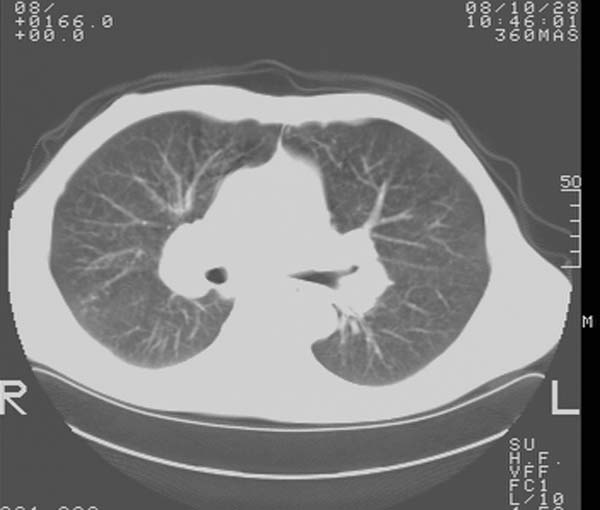

m,65y。半年前发现颈小结节,逐渐增多增大,现双侧耳后、颌下及颈部表浅淋巴肿大。胸片示双肺门增大。外院曾穿刺诊断为淋巴结核。在我科作胸腹部ct,我们觉得外院病检有误。现将图像上传请战友讨论。

纵隔内及腹膜后广泛淋巴结肿大,脾大,肝内似可见低密度影,结合病史半年前发现颈小结节,逐渐增多增大,现双侧耳后、颌下及颈部表浅淋巴肿大。考虑淋巴瘤。

纵隔,双肺门腹膜后多发淋巴结重大,非融合,肝脾轻度肿大,双肺野弥漫性小结节;考虑淋巴瘤,结节病可能性

纵隔内,双肺门、腋窝及腹膜后多发肿大淋巴结影,肺内小结节影,肝脾体积增大,支持淋巴瘤。肝内多发低密度影,考虑小囊肿。

考虑淋巴瘤肺、肝内转移,脾脏肿大。